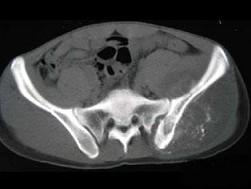

问题 男,35岁,左髂部剧烈疼痛,尤以夜间明显,可摸到肿物,结合图像,最可能的诊断是?(?) {图1} {图2} {图3}

选项 A.骨巨细胞瘤 B.软骨肉瘤 C.骨转移瘤 D.骨肉瘤 E.软骨瘤

答案 D